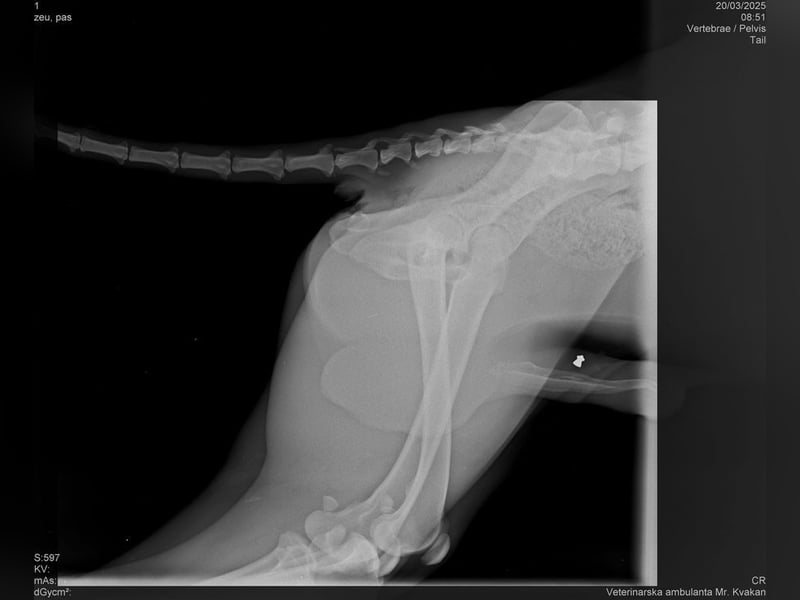

Bemerkungen: Lehmann wurde mit einer Verletzung am Hinterbeinchen gefunden. Ein Röntgenbild finden Sie in der Bildergalerie.